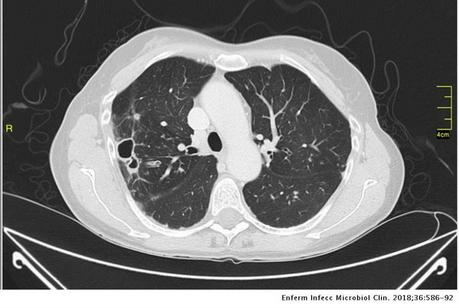

Vía aérea y pulmones: Con ventana para pulmón se observa hacia el segmento superior del lóbulo inferior derecho la presencia de una lesión cavitada, la cual tiene un diámetro máximo de 3.3 cm, además ambos pulmones presentan algunas áreas con patron micronodular, predominantemente hacia lóbulos medio y língula. La tráquea se aprecia central, sin alteraciones.

- ESTUDIO TOMOGRÁFICO DE TORAX QUE MUESTRA HALLAZGOS QUE PUDIERAN CORRESPONDER CON PROCESO INFECCIOSO DE TIPO GRANULOMATOSO NO TUBECULOSO (MICOBACTERIUM AVIUM) COMO PRIMERA POSIBILIDAD, SIN EMBARGO, LA POSIBILIDAD DE QUE PROCESO TUBERCULOSO O FIMICO NO PUEDE SER DESCARTADO.

La infección pulmonar por MAC y en general por el grupo de MNT se ha clasificado en formas fibrocavitarias o multibacilares, con patrón destructivo semejante a la tuberculosis pulmonar cavitada clásica, con tinción habitualmente positiva para bacilos ácido-alcohol resistentes, y formas nodulares-bronquiectásicas, paucibacilares y más indolentes que plantean dudas de diagnóstico diferencial de enfermedad pulmonar lentamente progresiva frente a colonización respiratoria transitoria de la vía aérea por MNT.